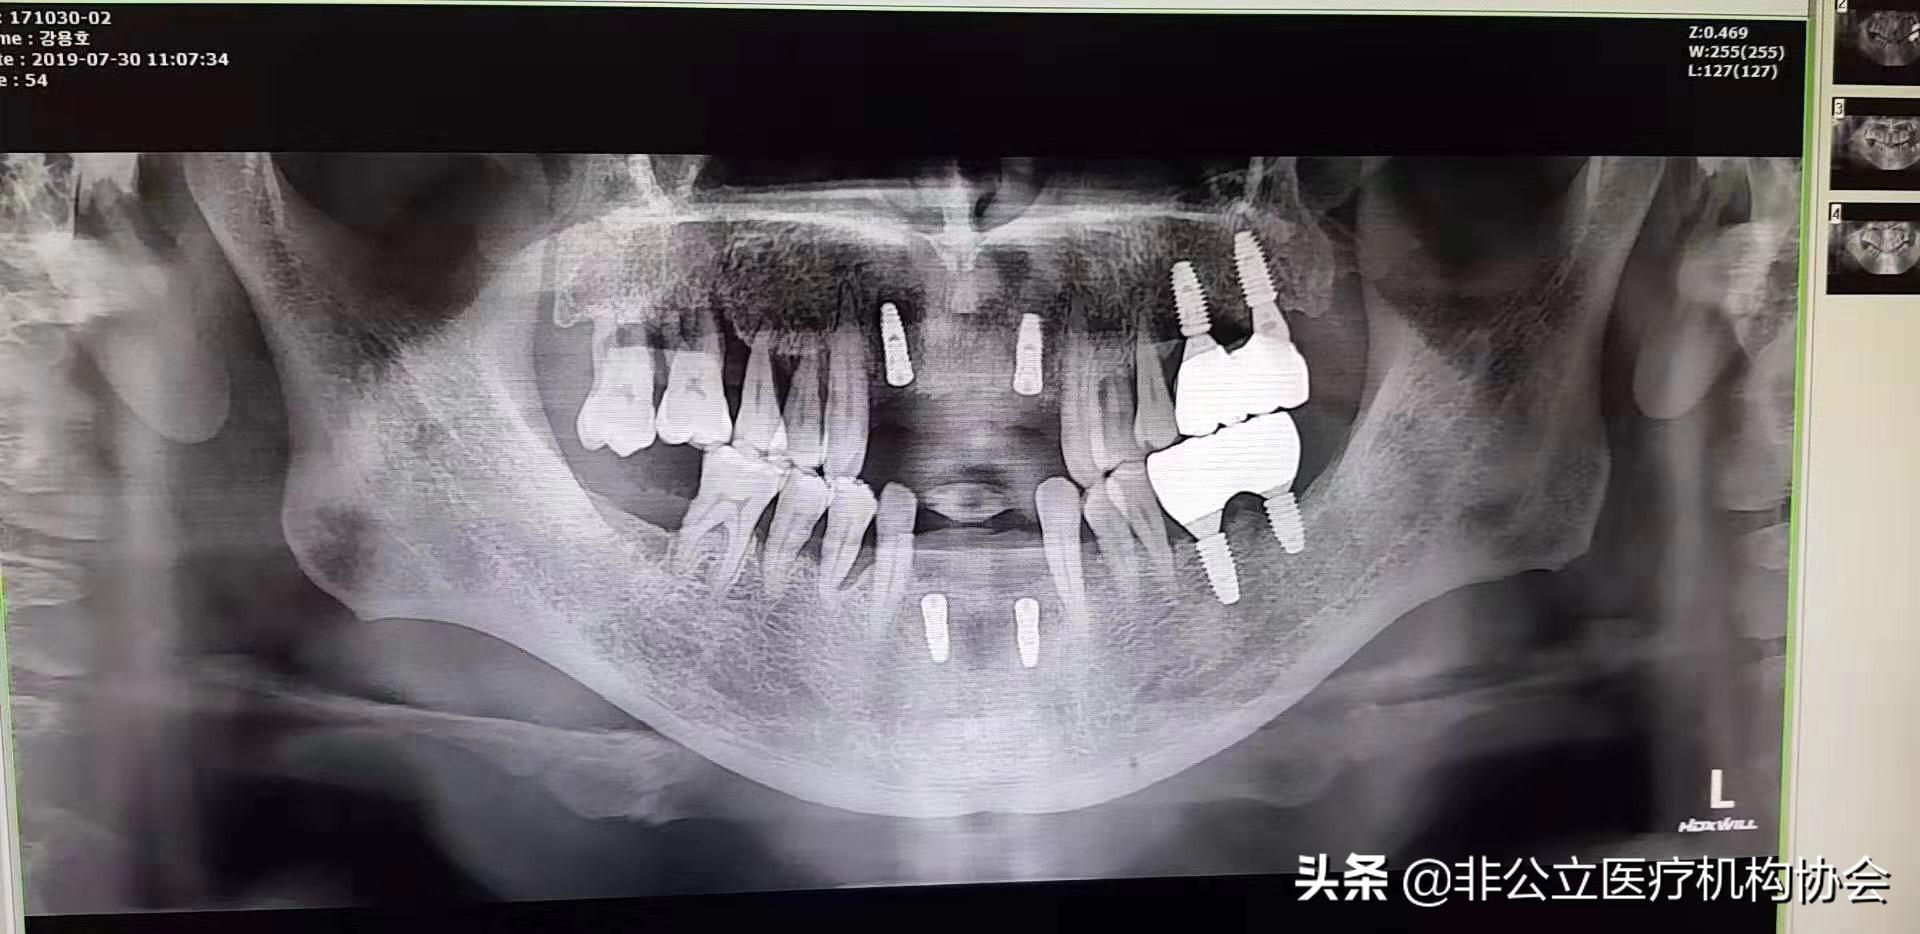

54歲患者術(shù)后X光照片

患者第二天來(lái)診所復(fù)診,上下頜恢復(fù)好,有一點(diǎn)輕微腫。

此病例第題部分修復(fù)完畢,一般經(jīng)過(guò)3~6個(gè)月的愈合時(shí)間,骨與種植體結(jié)合,義齒便可修復(fù)在種植體上制作完成了。